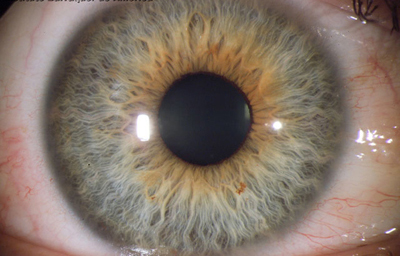

El Color del Iris

El Iris en general es muy pigmentado con colores que comúnmente van del marrón, avellana, gris, verde y azul. Existen los iris sin pigmento en el Albinismo oculo-cutáneo en cuyo caso se ven blanco/rosados.

El color del Iris es un fenómeno complejo por efectos combinados por la textura, la pigmentación y el tejido fibrovascular del estroma, junto con la constitución epigenética del individuo. Desde el punto de vista óptico, la simple absorción o reflexión selectiva por algunas moléculas, como la hemoglobina o el colágeno del estroma que son componentes no pigmentados, puede tener influencia en el color que es observado.

A pesar de la gran variedad en el color del Iris, el único pigmento que contribuye en forma sustancial es la melanina; su cantidad, es uno de los factores que determina el color del iris en una persona. Estructuralmente el color depende de la cantidad variable de eumelanina (melaninas marron/negra) y pheomelanina (melaninas rojo/amarillo) producidas por los melanocitos derivados de la Cresta Neural. El grado de dispersión de la melanina que yace en racimos subcelulares en los melanosomas, tiene cierta influencia en el color que se observa, pero el grado de dispersión no es reversible ya que los melanosomas no son moviles.

En los humanos el Iris tiene el mismo color en los dos ojos siendo sutilmente diferentes en su desarrollo y paisaje final; pero existen variantes2